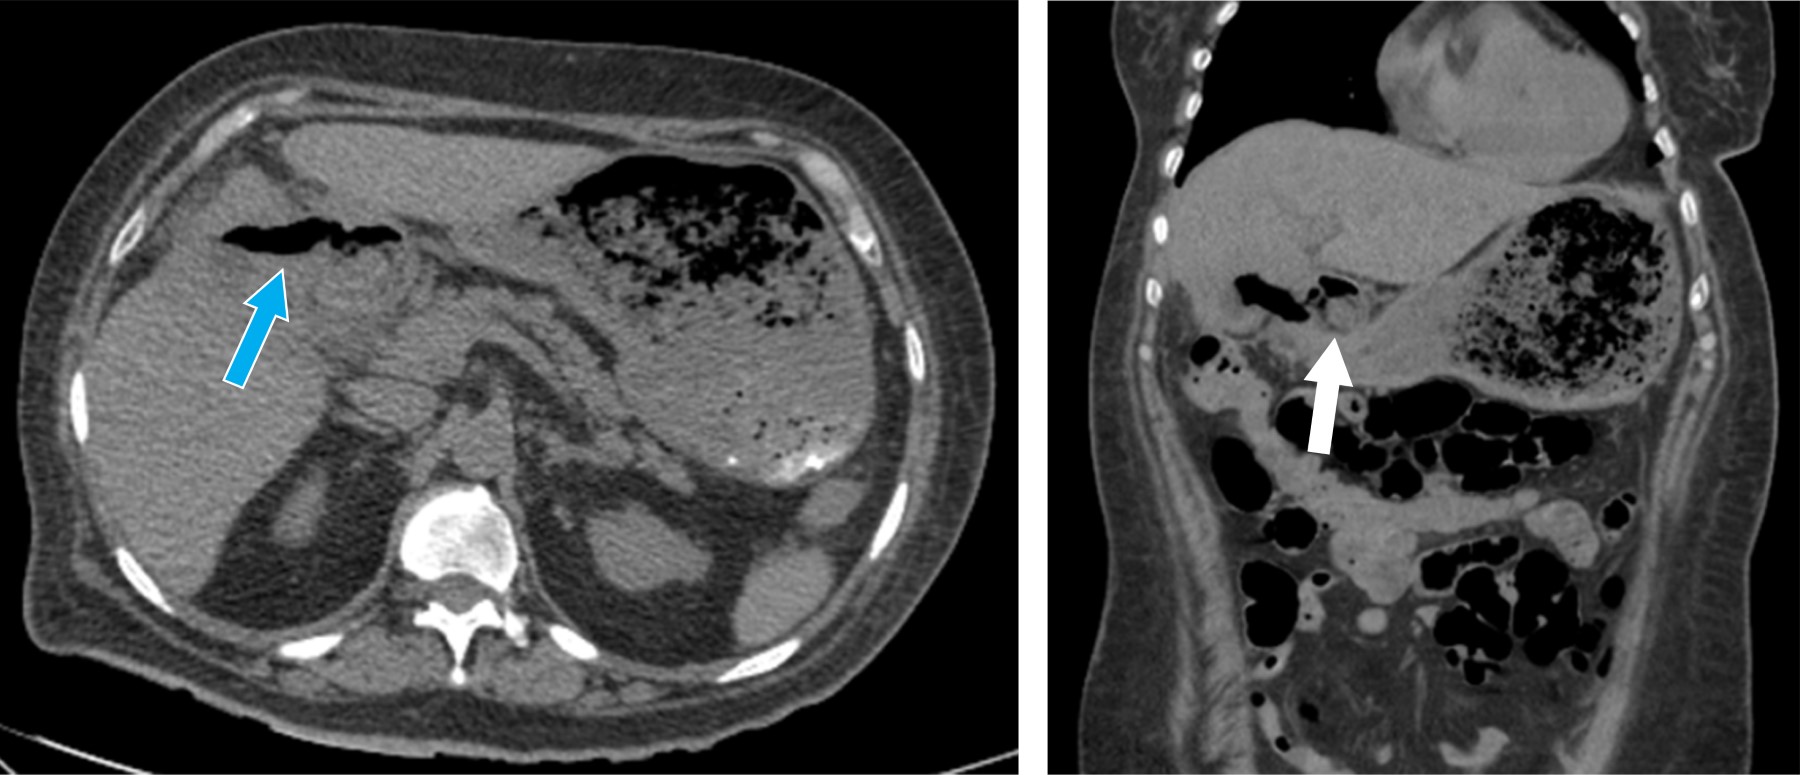

Se trata de paciente femenino de 59 años, que cuenta con antecedente de diabetes mellitus tipo 2 de larga evolución. Acude al servicio de urgencias por presentar dolor de tipo cólico en hipocondrio derecho de seis meses de evolución, de intensidad 6/10 en la escala análoga visual, sin irradiaciones, asociado a la ingesta de alimentos colecistoquinéticos, sin atenuantes, niega fiebre, ictericia, coluria o acolia. A la exploración física, con dolor a la palpación profunda en hipocondrio derecho, Murphy ausente, sin datos de irritación peritoneal. Cuenta con los siguientes laboratorios: hemoglobina 12.9 g/dl, hematocrito 37%, leucocitos 9.4 × 103/μl, plaquetas 360 × 103/μl, glucosa 178 mg/dl, creatinina 0.7 mg/dl, sodio 145 mEq/l, potasio 3.7 mEq/l, cloro 105 mEq/l, bilirrubina total 0.7 mg/dl, fosfatasa alcalina 55 U/l. Se realiza ultrasonido de hígado y vías biliares, el cual revela vesícula biliar con aumento de su ecogenicidad en toda su extensión, provocando fenómeno Wall-Echo-Shadow (WES) con dimensiones de 52.7 × 29.4 × 18.7 mm. Con pared no valorable, colédoco de 5.8 mm, sin evidencia de litos en su interior (Figura 1). Se realiza rastreo tomográfico donde se observa vesícula con volumen de 13.2 cm3, heterogénea, con presencia de densidad aire, pared engrosada de manera regular con presencia de calcificaciones, estómago distendido, con presencia de imagen hiperdensa en su interior (probable lito) (Figura 2).

Figura 1

Figura 2